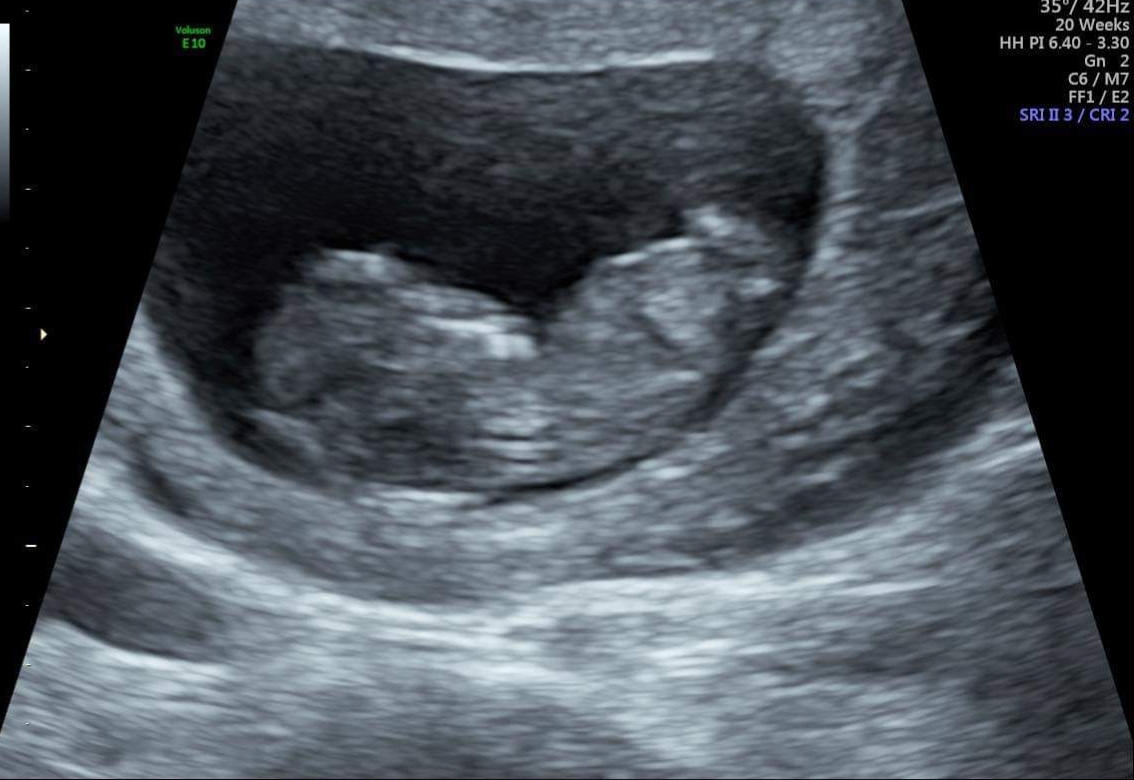

A couple from the 11 plus 4 just in case ...

Boys and girls are identical at that stage. The thing you see could turn into a penis or clitoris depending on the hormones the baby releases during development. Just can't tell reliably till the end of the 12th week at the soonest.